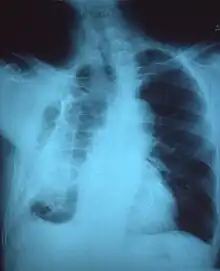

A fibrothorax can typically be diagnosed by taking an appropriate medical history in combination with the use of appropriate imaging techniques such as a plain chest X-ray or CT scan.[3] These imaging techniques can detect fibrothorax and pleural thickening that surround the lungs.[7] The presence of a thickened peel with or without calcification are common features of fibrothorax when imaged.[3] CT scans can more readily differentiate whether pleural thickening is due to extra fat deposition or true pleural thickening than X-rays.[3]

If a fibrothorax is severe, the thickening may restrict the lung on the affected side causing a loss of lung volume.[7] Additionally, the mediastinum may be physically shifted toward the affected side.[3] A reduction in the size of one side of the chest (hemithorax) on an X-ray or CT scan of the chest suggests chronic scarring.[6] Signs of the underlying disease causing the fibrothorax are also occasionally seen on the X-ray.[6] A CT scan may show features similar to those seen on a plain X-ray.[7] Lung function testing typically demonstrates findings consistent with restrictive lung disease.[6]

Autopsy specimen showing extensive pleural fibrosis